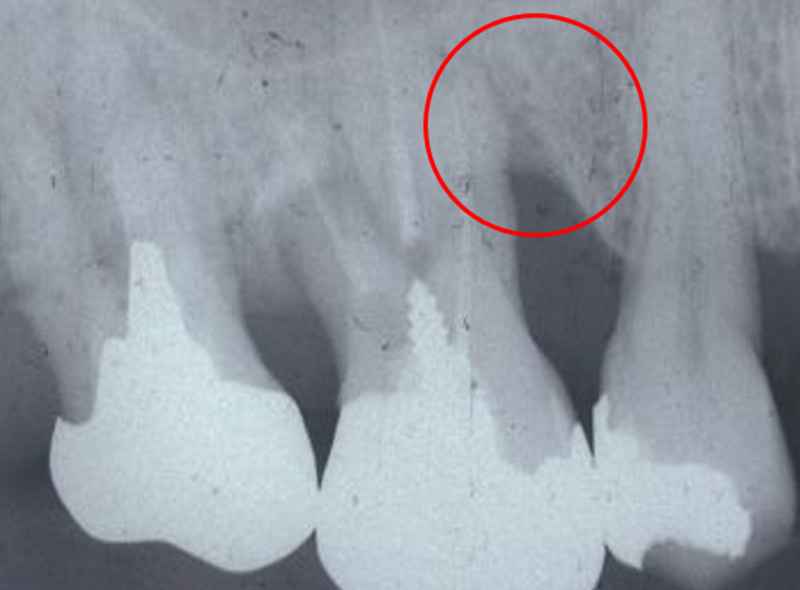

根分岐部病変

(根が分岐している奥歯に生じた歯周病)

の治療

~専門医・指導医による歯周病治療3~

治療の概要

根分岐部病変は、歯根が2本以上ある歯の根分岐部まで進行した歯周病で、歯石除去が難しくブラッシングもしにくい場所のため、症状が出にくく治療が難しいのが特徴です。歯周病を制するには根分岐部病変を制する必要があり、進行した場合は抜歯の選択肢が検討されることも少なくありません。

さっさと抜いてインプラント、ではなく、根分岐部病変をどう考えてどう生かすかが歯周病専門医の姿勢や力量です。

治療例の紹介